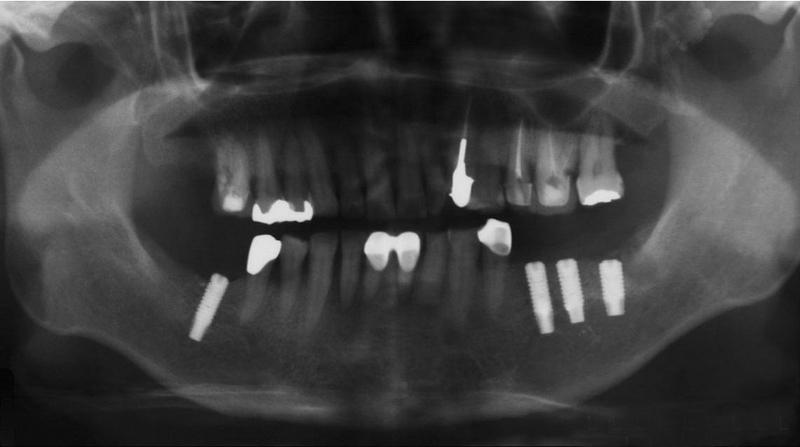

Sterowana regeneracja kości. Poszerzenie wyrostka zębodołowego żuchwy.